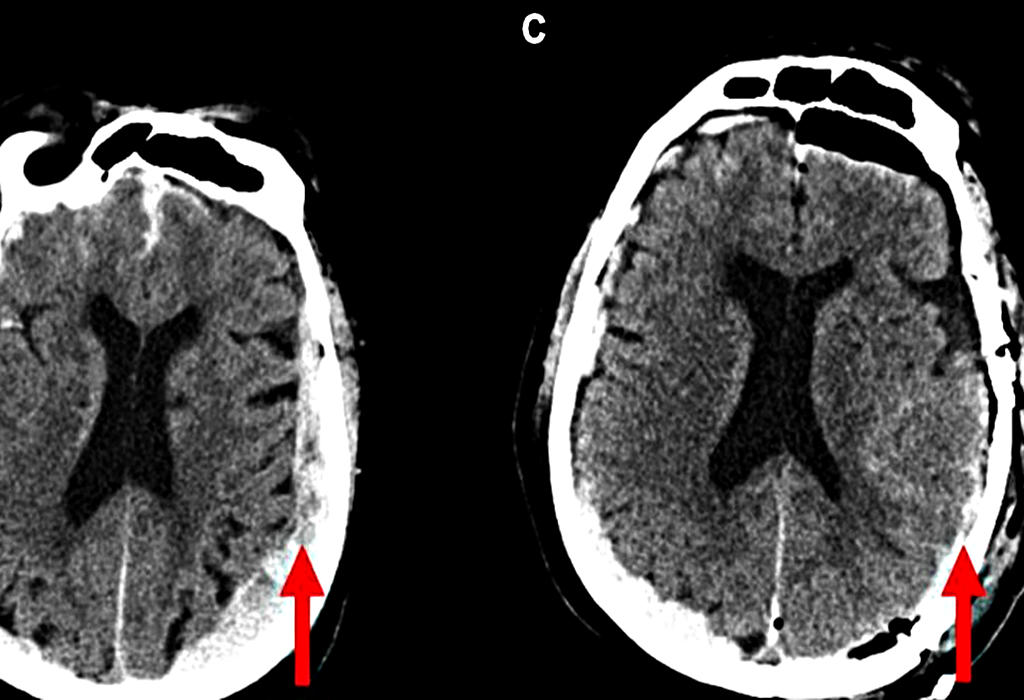

Skeniranje mozga

Prvo skeniranje umirućeg mozga otkriva posljednje trenutke

mozak